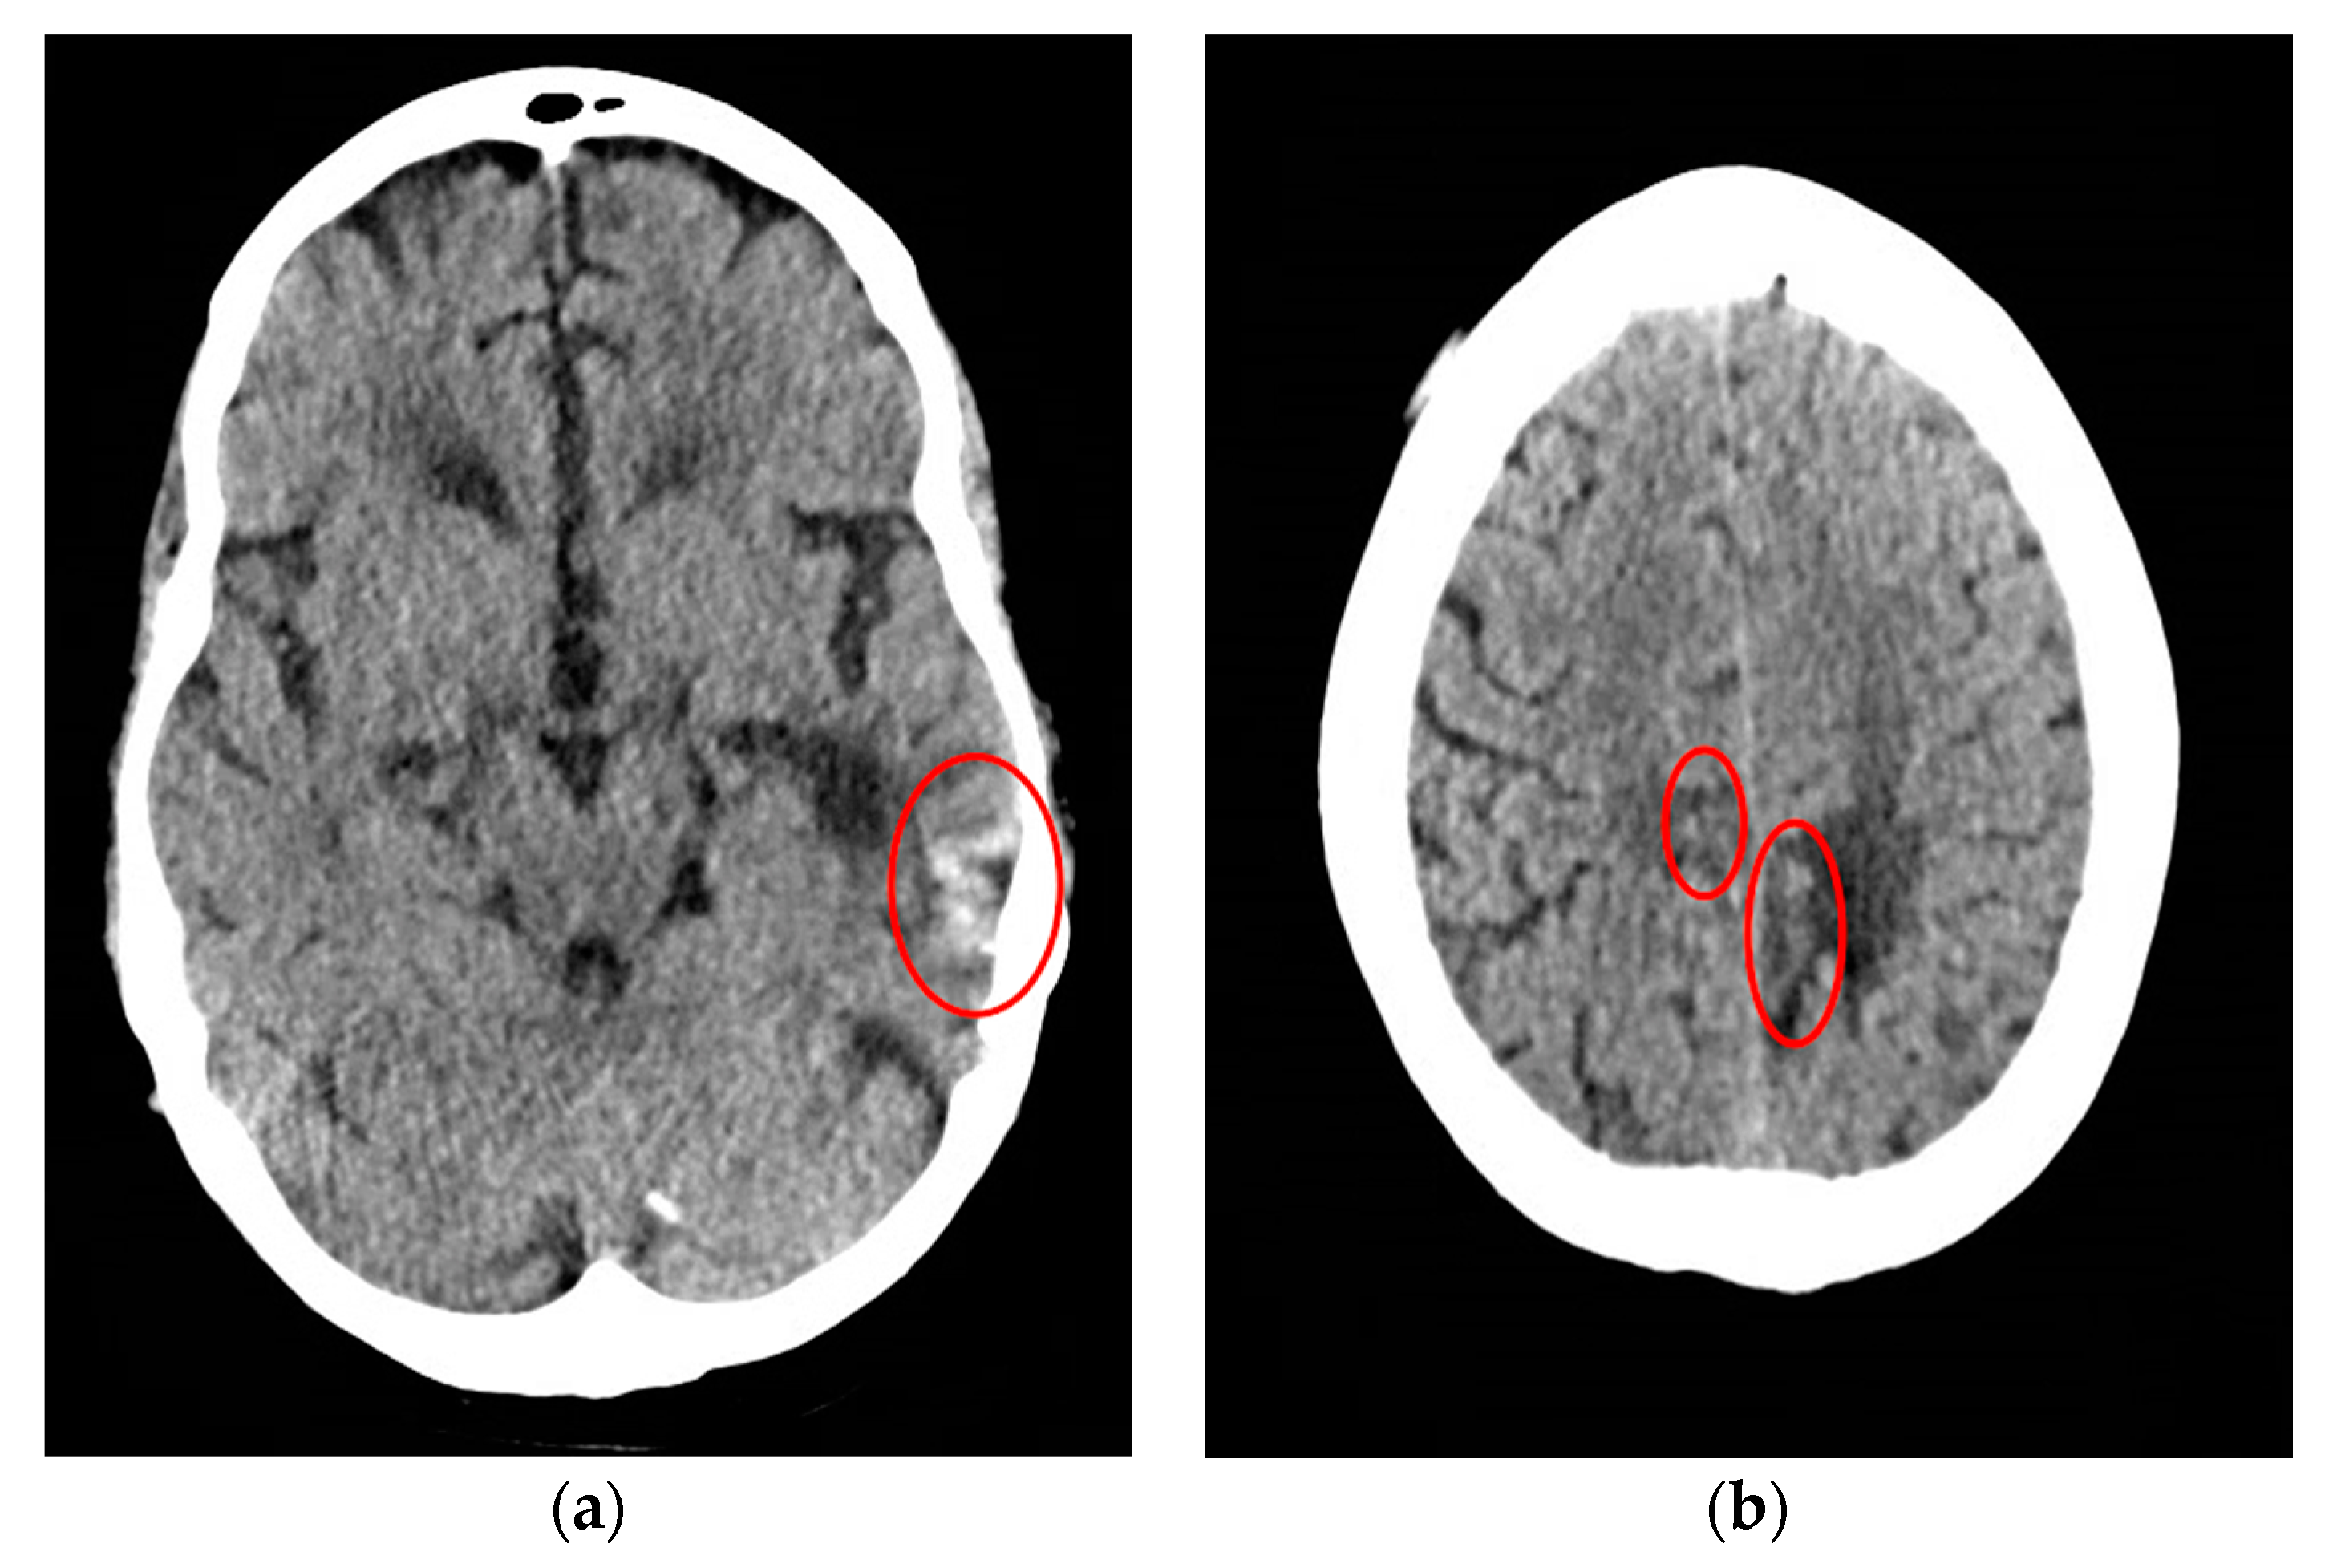

CT scan of the head was reassuring, showing no significant changes from the patient’s previous MRI, performed one month prior to this hospitalization. Unchanged lesions include: small inferolateral left temporal density, associated white matter low density, small medial right and left parietal occipital low densities, and a posterior cerebral white matter hypodensity (Figure 1). Patient’s EEG result read: abnormal EEG due to mild to moderate diffuse slowing, with excess low-moderate voltage polymorphic delta and theta activity (Figure 2).

Figure 2. Electroencephalogram (EEG) of a 61-year-old male with SCNS-DLBCL presenting with acute encephalitis. Consistent with an abnormal EEG reading due to mild-moderate diffuse slowing. This specific frame shows excess low to moderate voltage (15 to 40 uV) polymorphic delta and theta activity. Interpretation of this EEG suggests mild to moderate diffuse cerebral dysfunction. Technical information: Electrodes were placed according to the 10–20 International Electrode System. Digital EEG was recorded using the Natus Digital EEG System and EEG was reformatted into multiple montages as needed.